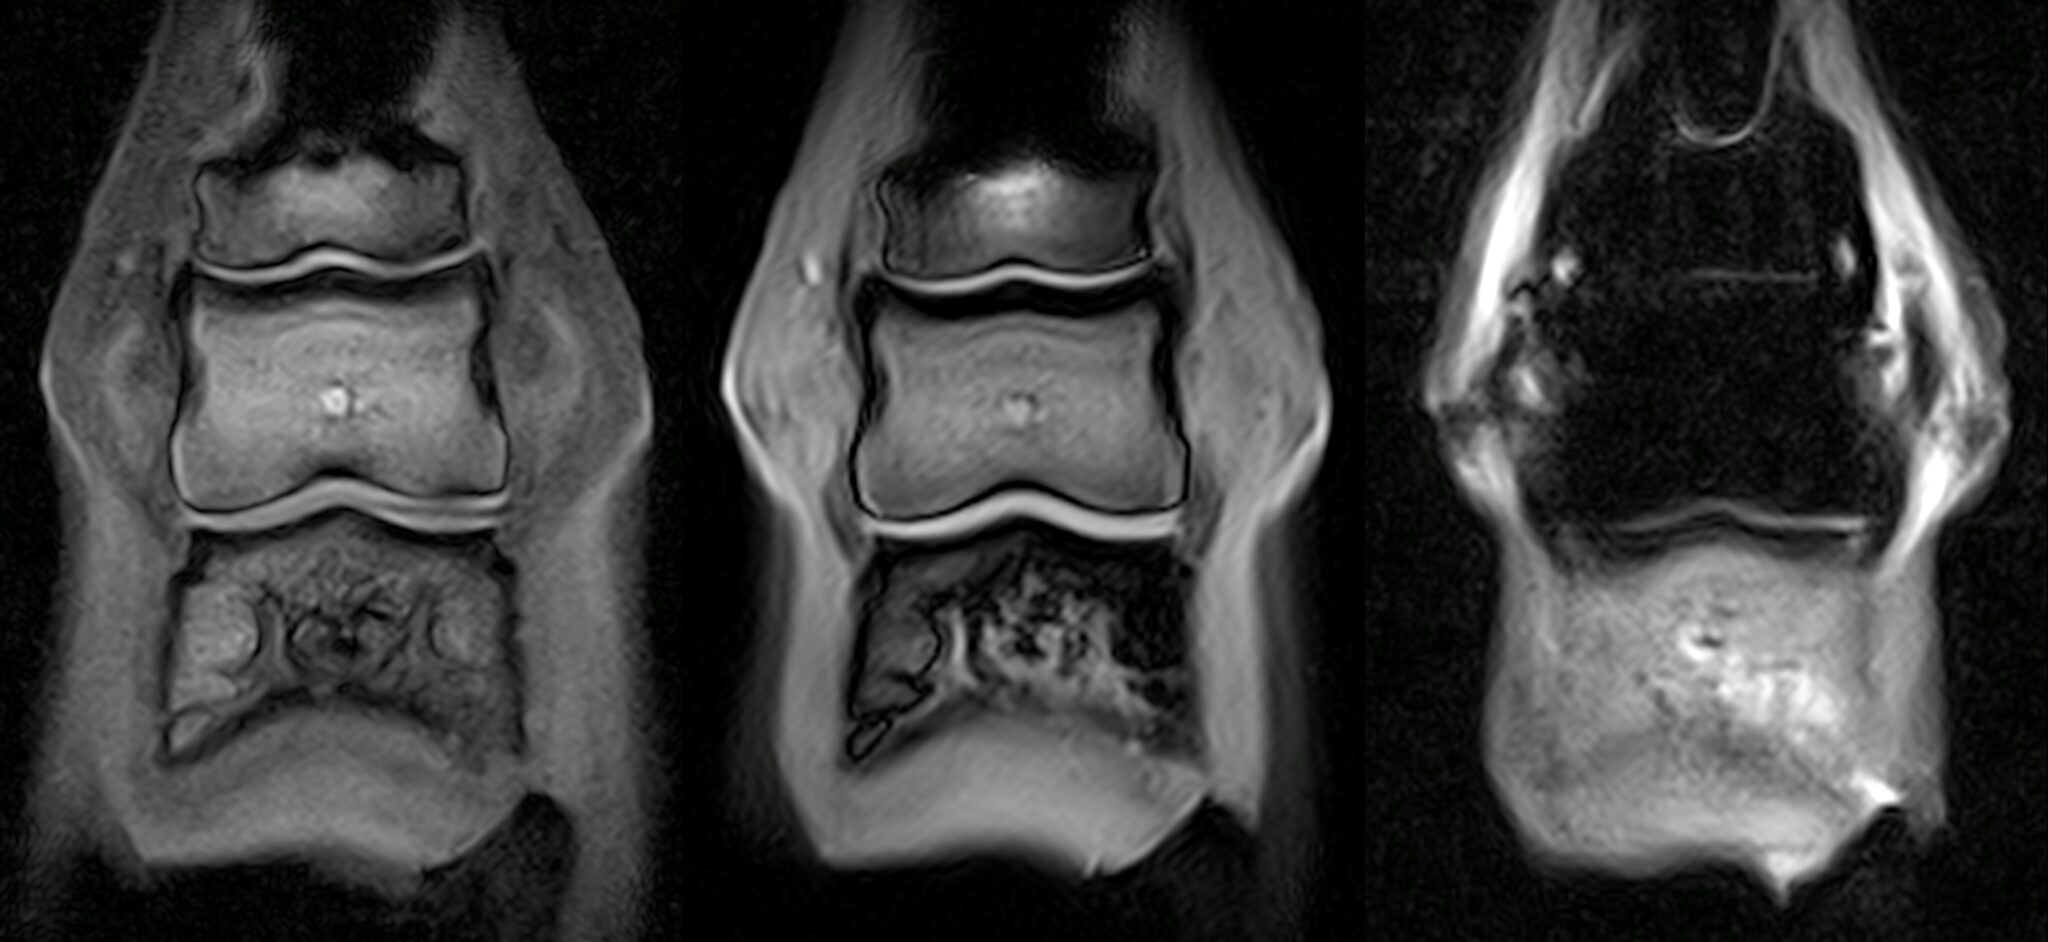

Figure 1 from Signal changes in standing resonance imaging of Pedal Osteitis Define Pedal osteitis in horses is a condition characterized by inflammation and damage to the pedal (coffin) bone within the hoof. Pedal osteitis simply means that the main bone (the pedal bone) enclosed by the horse’s foot is inflamed or bruised. Pedal osteitis is inflammation of the pedal bone. Pedal osteitis is a radiographic finding that describes demineralization and bone resorption. Pedal Osteitis Define.

Figure 2 from Signal changes in standing resonance imaging of Pedal Osteitis Define Pedal osteitis is a radiographic finding that describes demineralization and bone resorption of any aspect of the solar margin of the distal. Pedal osteitis is inflammation of the pedal bone. Pedal osteitis simply means that the main bone (the pedal bone) enclosed by the horse’s foot is inflamed or bruised. Pedal osteitis in horses is a condition characterized by inflammation. Pedal Osteitis Define.